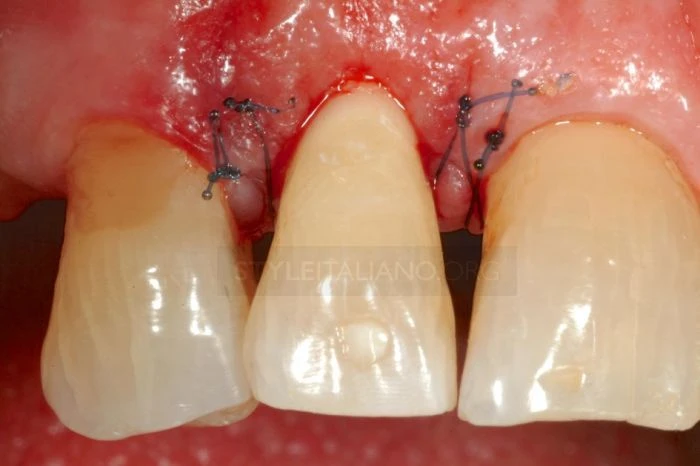

Vì những khó khăn do vết gãy gây ra các bác sĩ quyết định tạo một đường rạch trong rãnh lợi bằng dao phẫu thuật 5c

Cắt nhú lợi ngoài về phía cuống răng để bảo tồn đám rối mạch máu vùng lợi kẽ răng.

Sau khi lật vạt, thực hiện phẫu thuật tạo hình xương phía ngoài nhưng phải để chân răng có chiều cao tối thiểu 2mm so với mào xương ổ răng. 2mm này rất quan trọng để tạo khoảng trống đủ cho bám dính sinh học.

Đây là thời điểm để đặt tấm cao su cách ly.

Khâu vết mổ bằng chỉ không tiêu polyaminde monolament 5/00 để tránh mảng bám tích tụ trong vài ngày sau điều trị. Khâu 2 mũi rời ở vị trí nhú lợi gần và 2 mũi ở phía xa. Cắt chỉ sau 2 tuần